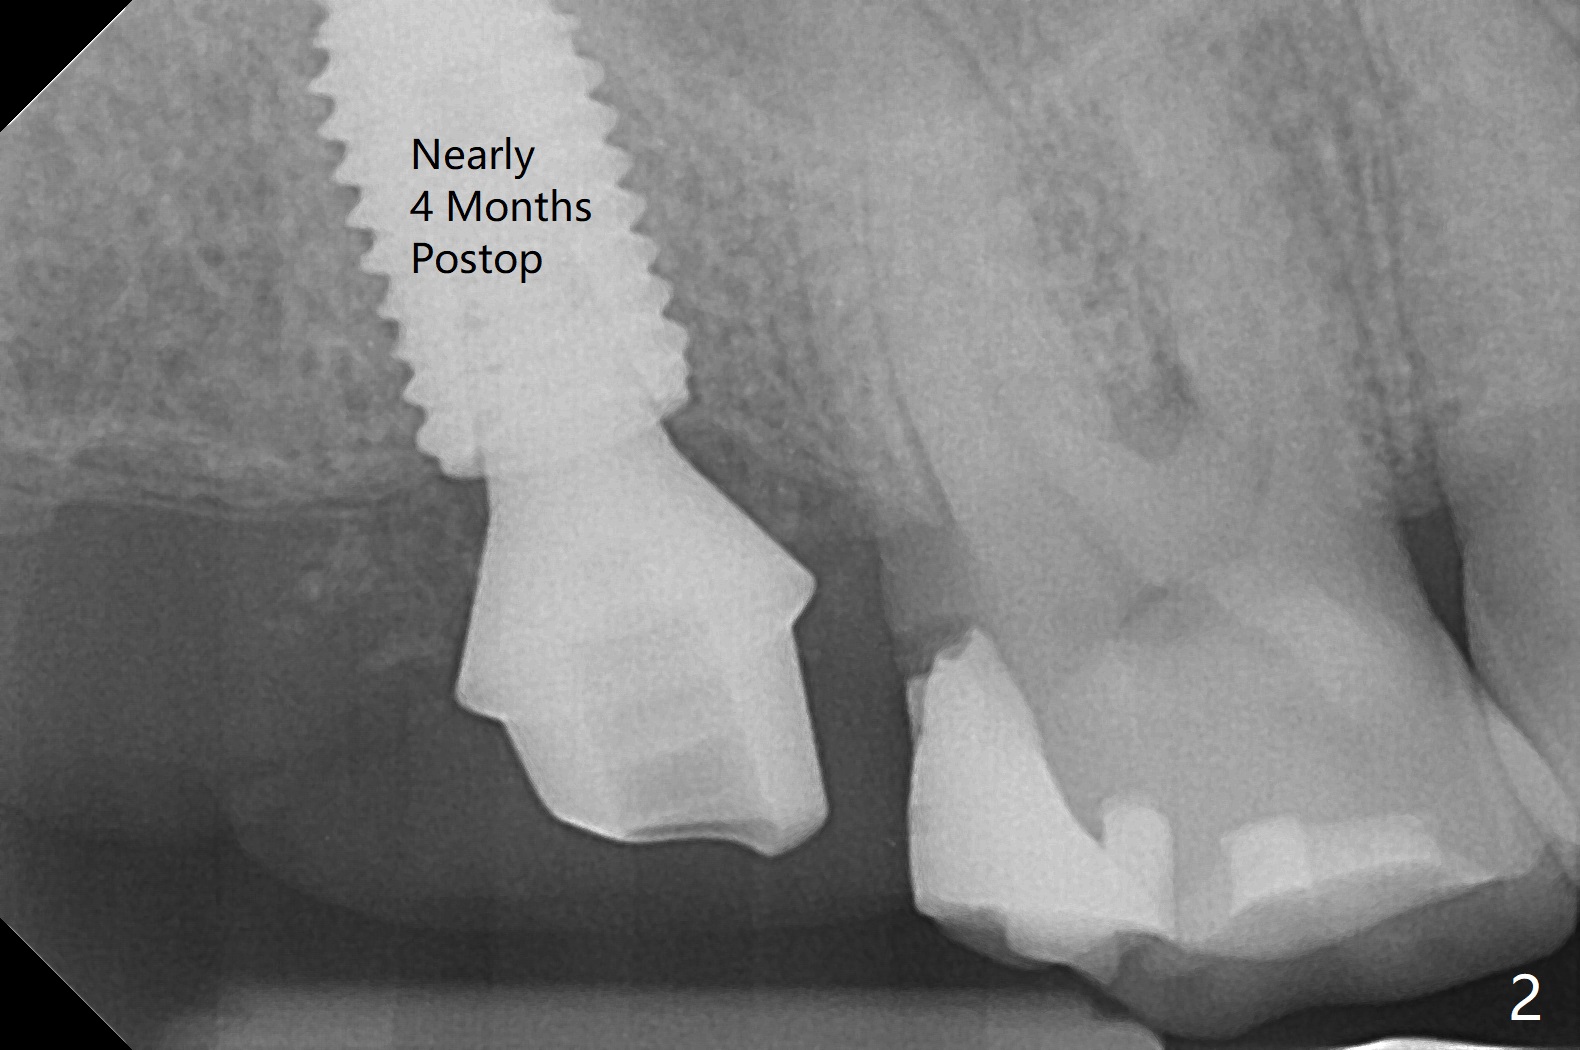

A 5x10 mm implant, placed in the buccal socket, achieves insertion torque of >55 Ncm after underprep (last drill 4 mm, as compared to 4.5 mm for normal prep). There is limited break of the sinus floor (Fig.1 arrowheads). No treatment is rendered for the mucocele. The implant heals without tenderness over the anterior sinus wall nearly 4 months postop (Fig.2). A crown is cemented 6 months postop (Fig.3 (5.2x4(4) mm abutment)); there is no gap between the abutment and implant, as compared to Fig.1,2 (6.5x4(3) mm). The implant functions without sign or symptom of bilateral sinusitis (no percussion associated with the tooth #13) 11 months post cementation (Fig.4). In fact the abutment is incompletely seated (Fig.5: <). Bone profile drill should be used to trim the mesial crest before reseating crown/abutment.